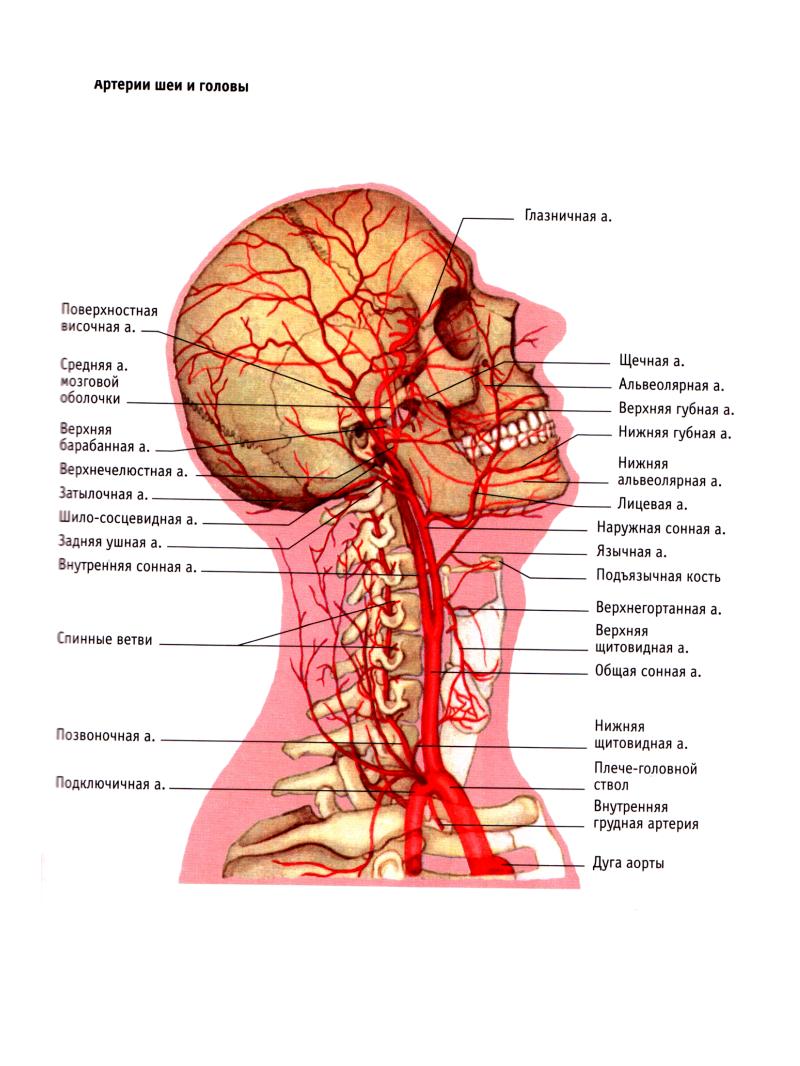

Анатомия: Задняя соединительная артерия мозга

Раздел: Фотоэссе